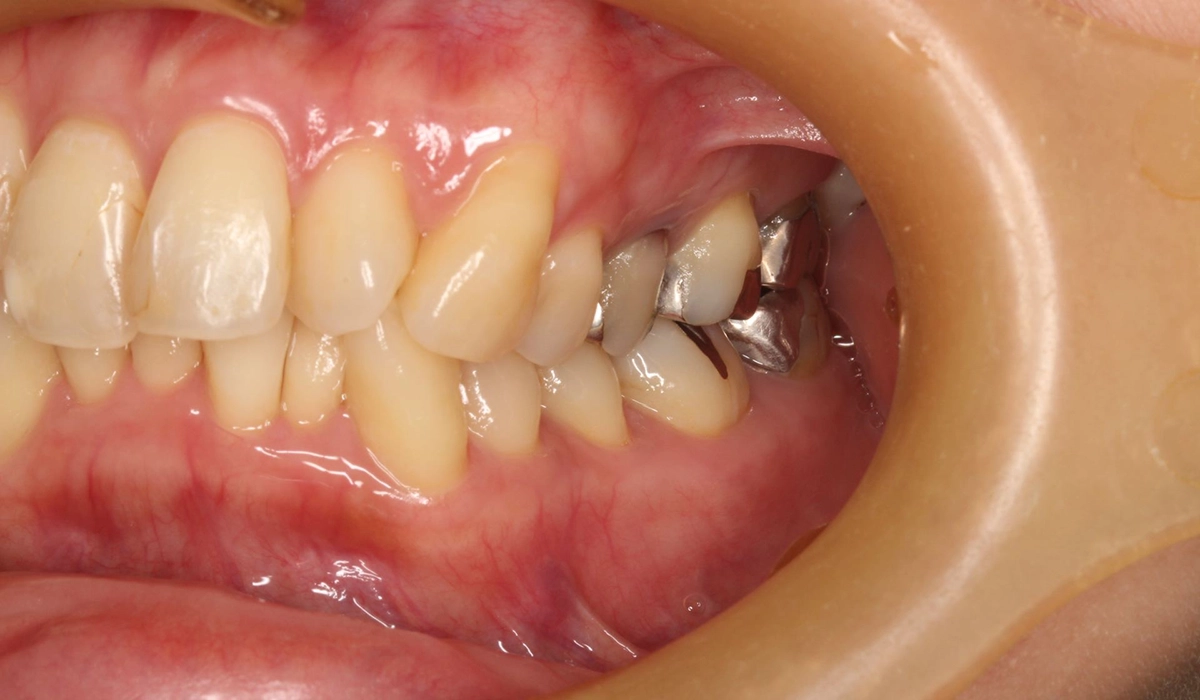

術前:右側

術後:右側